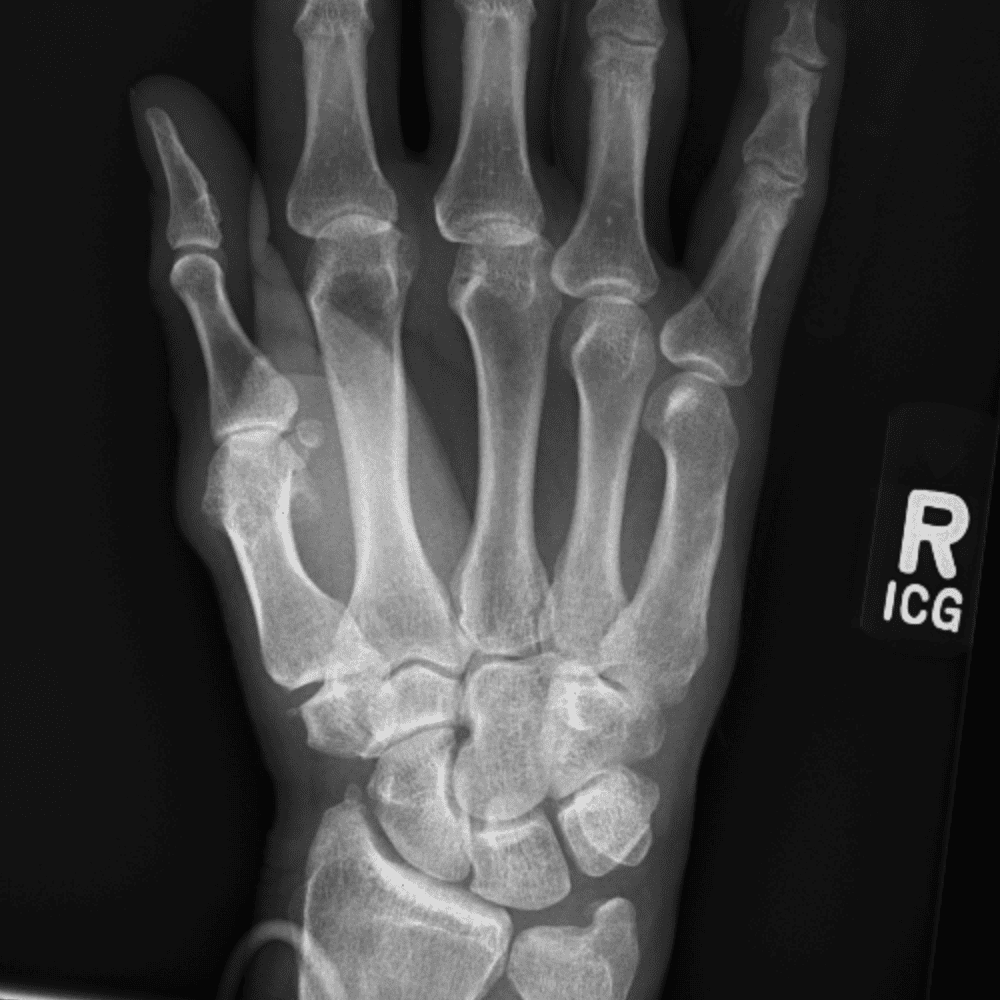

Simuliert den Dienst durch subtile oder schwierige Fälle und einige Normalbefunde.

30 Fälle